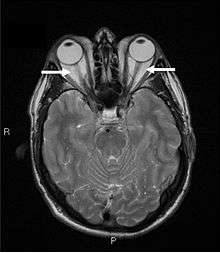

Magnetic Resonance Imaging of the orbits, showing congestion of the retro-orbital space and enlargement of the extraocular muscles (arrows), consistent with the diagnosis of Graves' Ophthalmopathy.

Orbital imaging is an interesting tool for the diagnosis of Graves' ophthalmopathy and is useful in monitoring patients for progression of the disease. It is, however, not warranted when the diagnosis can be established clinically. Ultrasonography may detect early Graves' orbitopathy in patients without clinical orbital findings. It is less reliable than the CT scan and magnetic resonance imaging (MRI), however, to assess the extraocular muscle involvement at the orbital apex, which may lead to blindness. Thus, CT scan or MRI is necessary when optic nerve involvement is suspected. On neuroimaging, the most characteristic findings are thick extraocular muscles with tendon sparing, usually bilateral, and proptosis.